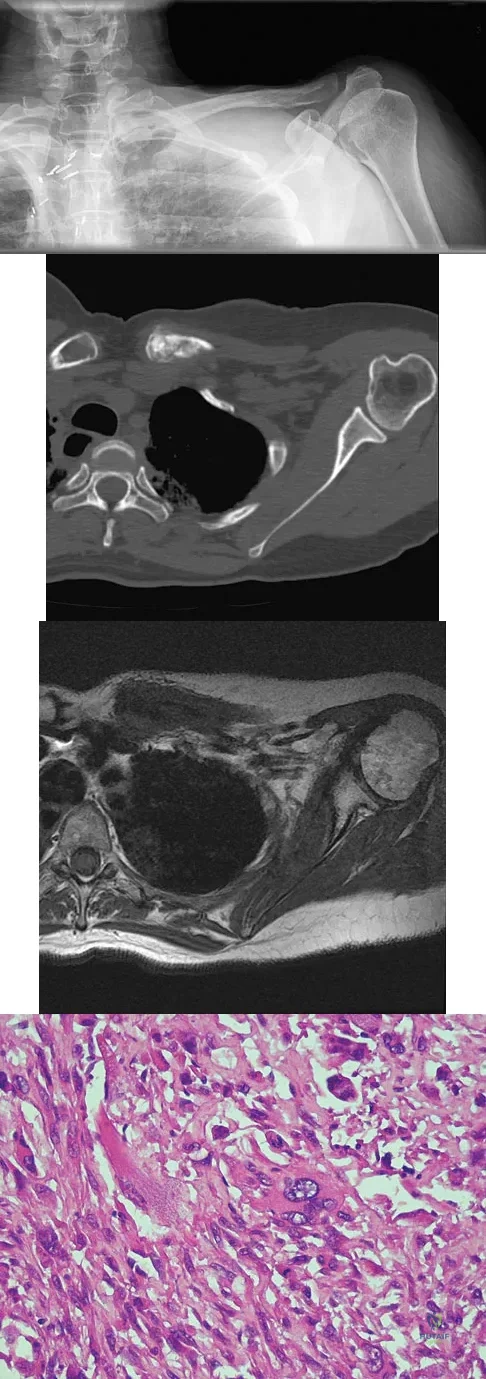

A 47-year-old woman has had left medial clavicle pain for the past 6 months. History is remarkable for mediastinal non-Hodgkin's lymphoma, treated with mantel radiation 22 years ago. A radiograph, CT scan, MRI scan, and a biopsy specimen are shown in Figures 68a through 68d. What is the most likely diagnosis?

Explanation